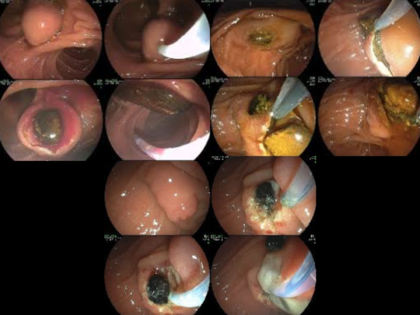

El objetivo es canular la papila y uno o los dos conductos (colédoco, Wirsung). Esta maniobra consiste en introducir en la papila un pequeño tubo plástico (catéter o cánula). Para llegar hasta la zona de la papila se utiliza un endoscopio o sonda óptica flexible que se introduce por la boca. Habitualmente, se emplea un endoscopio especial para la CPRE llamado duodenoscopio. La canulación de la papila y del conducto deseado (colédoco y/o Wirsung) es uno de los puntos más cruciales en la CPRE. En ocasiones, esta maniobra es muy compleja y, de hecho, la CPRE se considera como una de las intervenciones más difíciles de la Endoscopia Digestiva. Una vez canulada la papila se inyecta a través del catéter un contraste radiológico. De esta forma se “dibujan” los conductos que pueden observarse con radiografías fijas o bien de forma dinámica (fluoroscopia). Por lo tanto, la CPRE se realiza habitualmente en una sala provista de rayos X. Para que el paciente esté tranquilo durante la CPRE, pueden utilizarse distintos tipos de sedación: anestesia general, sedación profunda o sedación consciente.

Una de las maniobras terapéuticas más frecuentes es seccionar (cortar) el músculo esfinteriano de la papila para agrandar su abertura al duodeno. Es lo que se denomina esfinterotomía o papilotomía, que puede hacerse en la vertiente del colédoco (esfinterotomía biliar), en la del páncreas (esfinterotomía pancreática), o en las dos. La esfinterotomía se realiza pasando una corriente eléctrica a través de un catéter especial denominado esfinterotomo para cortar la papila. El orificio papilar puede también agrandarse dilatándolo con un balón. Es lo que se denomina esfinteroplastia.

Algunas otras de las múltiples intervenciones que pueden llevarse a cabo en la CPRE son: extracción de piedras en el colédoco (coledocolitiasis), colocación de tubos plásticos o metálicos (prótesis o stents) en el colédoco o páncreas para tratar estrecheces (estenosis), fístulas u otros problemas que afecten a los conductos. Estas prótesis pueden ser temporales o permanentes, según el tipo de obstrucción.